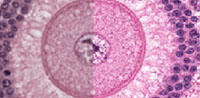

Histology is the study of the microanatomy of cells, tissues, and organs as seen through a microscope. It examines the correlation between structure and function.

Histology Guide teaches the visual art of recognizing the structure of cells and tissues and understanding how this is determined by their function. Rather than reproducing information found in a histology textbook, a user is shown how to apply this knowledge to interpret cells and tissues as viewed through a microscope.

Because of the high cost of purchasing (and maintaining) microscopes and preparing (or purchasing) slide collections, histology is often taught today without laboratories. A histology atlas is frequently used as a replacement. This is unfortunate because no matter how good the few images in a textbook or histology atlas are, they cannot replace the experience of viewing a specimen through a microscope.

Histology Guide solves this problem by recreating the look and feel of a microscope in an intuitive, browser-based interface.

Unlike low-resolution images, users can interactively explore these large images by zooming-and-panning in real-time. A software-based virtual microscope (Zoomify HTML5 Enterprise) allows the examination of large and small structures in the same specimen.

This approach provides a more engaging learning experience and sense of scale, proportion and context that is not possible with a traditional histology textbook or atlas.